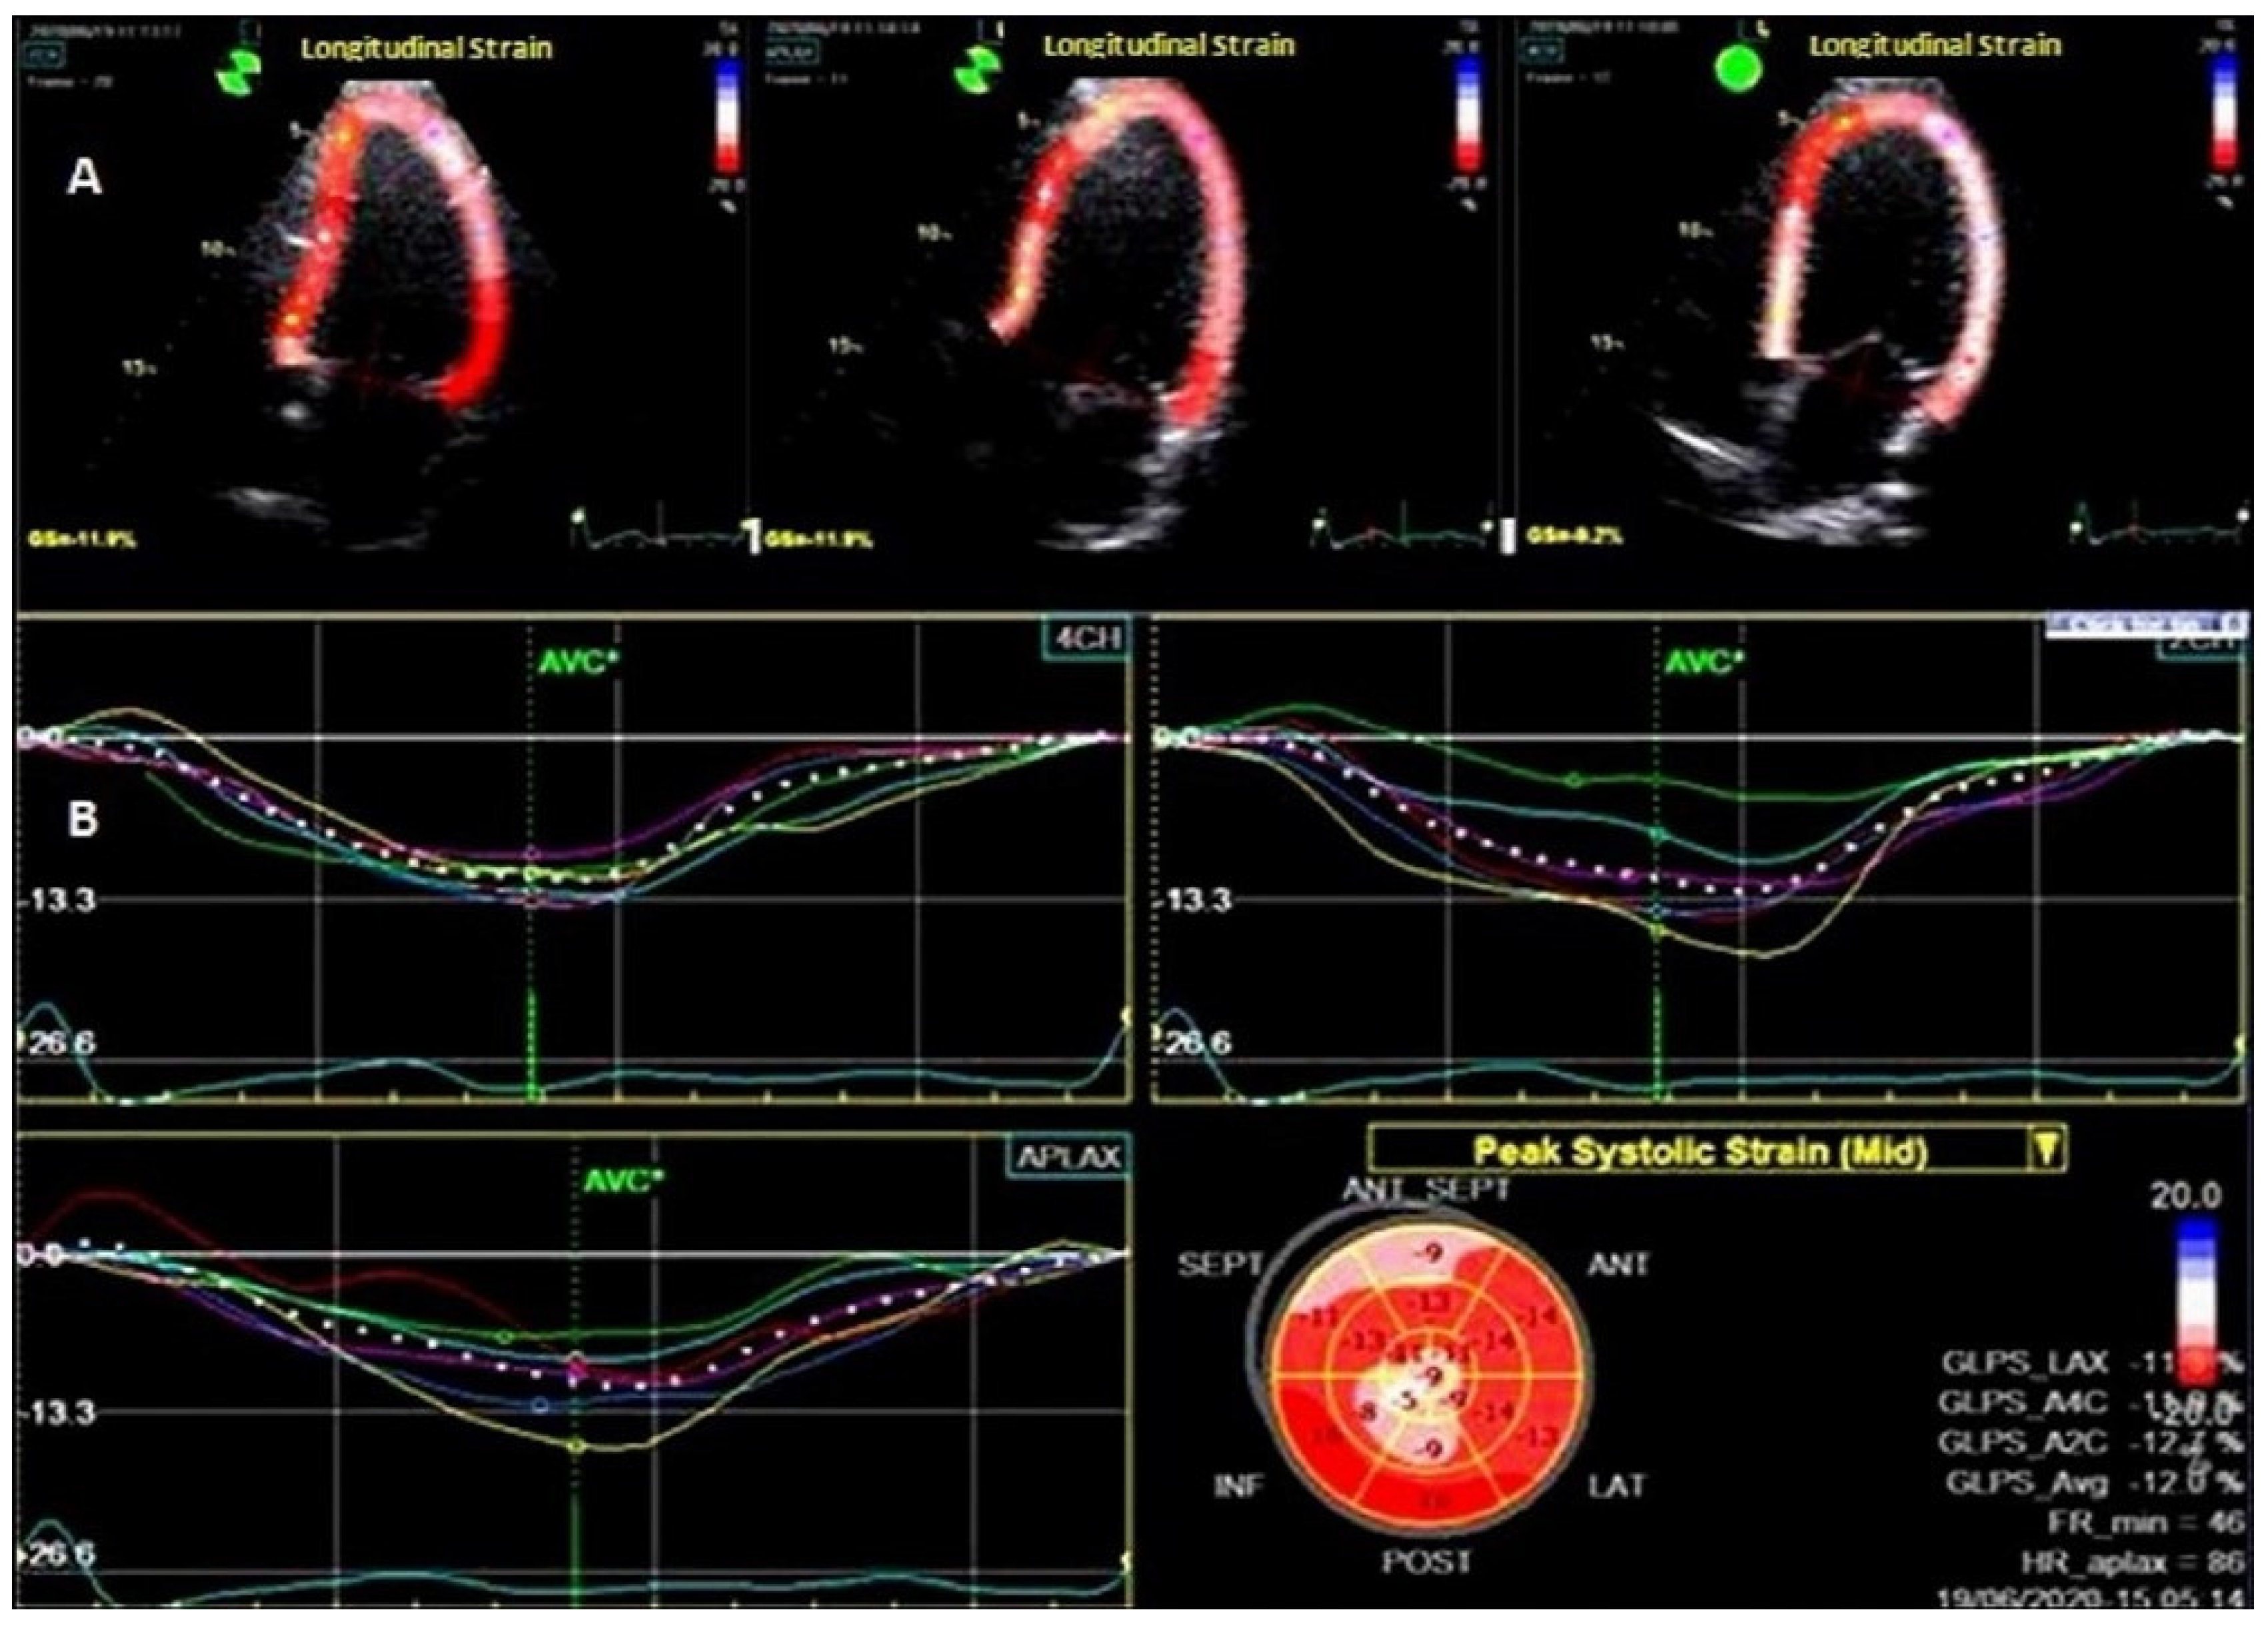

| GLS (%) | 20.1 ± 2.4 | 21.6 ± 2.1 | 0.0001 |

| GLS ≤ 18% | 34 (47%) | 13 (16%) | <0.0001 |